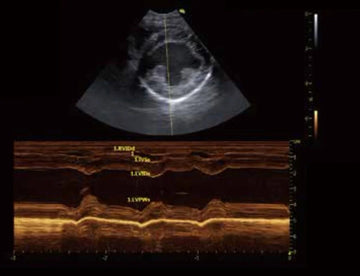

- Monitoreo en tiempo real: Permite evaluar el flujo sanguíneo y cambios en los órganos al instante.

- Otro uso fundamental de la ecografía es como herramienta de guía en procedimientos clínicos. Por ejemplo, en biopsias, los veterinarios pueden extraer muestras de tejidos específicos con precisión, reduciendo riesgos y complicaciones. Asimismo, puede utilizarse en drenajes de líquidos en casos de acumulación anormal, lo que mejora considerablemente la seguridad del paciente.